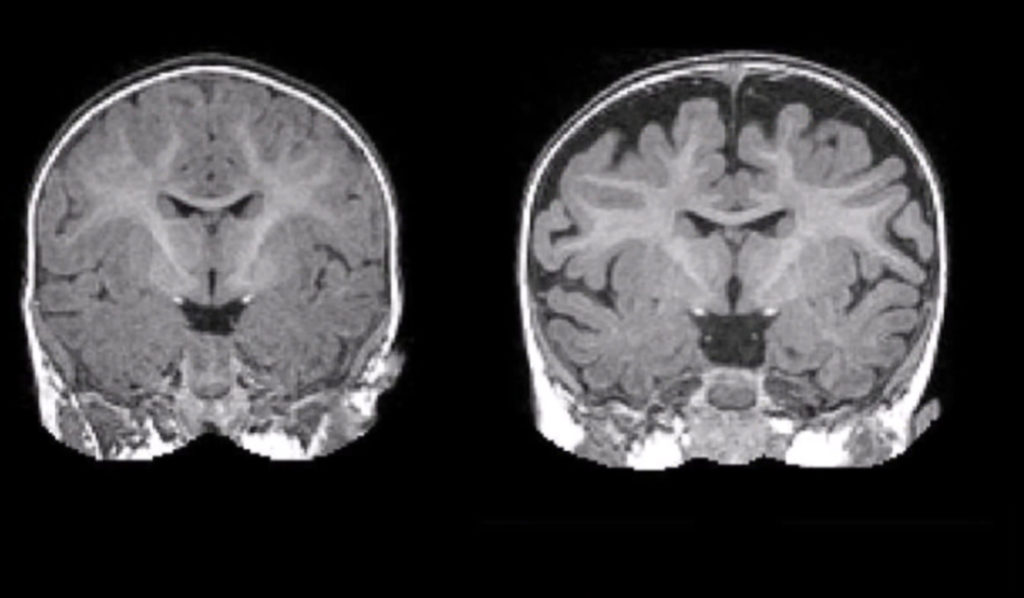

Ngày 16/7/1973, 4 ngày trước khi đột tử, Lý Tiểu Long điện thoại cho người bạn thân là Unicorn Chan, và cho biết anh thực sự lo lắng về những cơn đau đầu dữ dội mà anh đang phải chịu đựng. Lý Tiểu Long không biết rằng, kể từ khi dính đòn đó của người đàn ông lạ mặt, cơ thể của anh bắt đầu dần suy kiệt. Cú đánh âm ỉ phá hủy dần hệ thần kinh và dẫn đến phù não như kết luận của các bác sĩ pháp y đưa ra. Một điều khá trùng hợp là sau khi chết, não của Lý Tiểu Long to hơn người bình thường 175g.